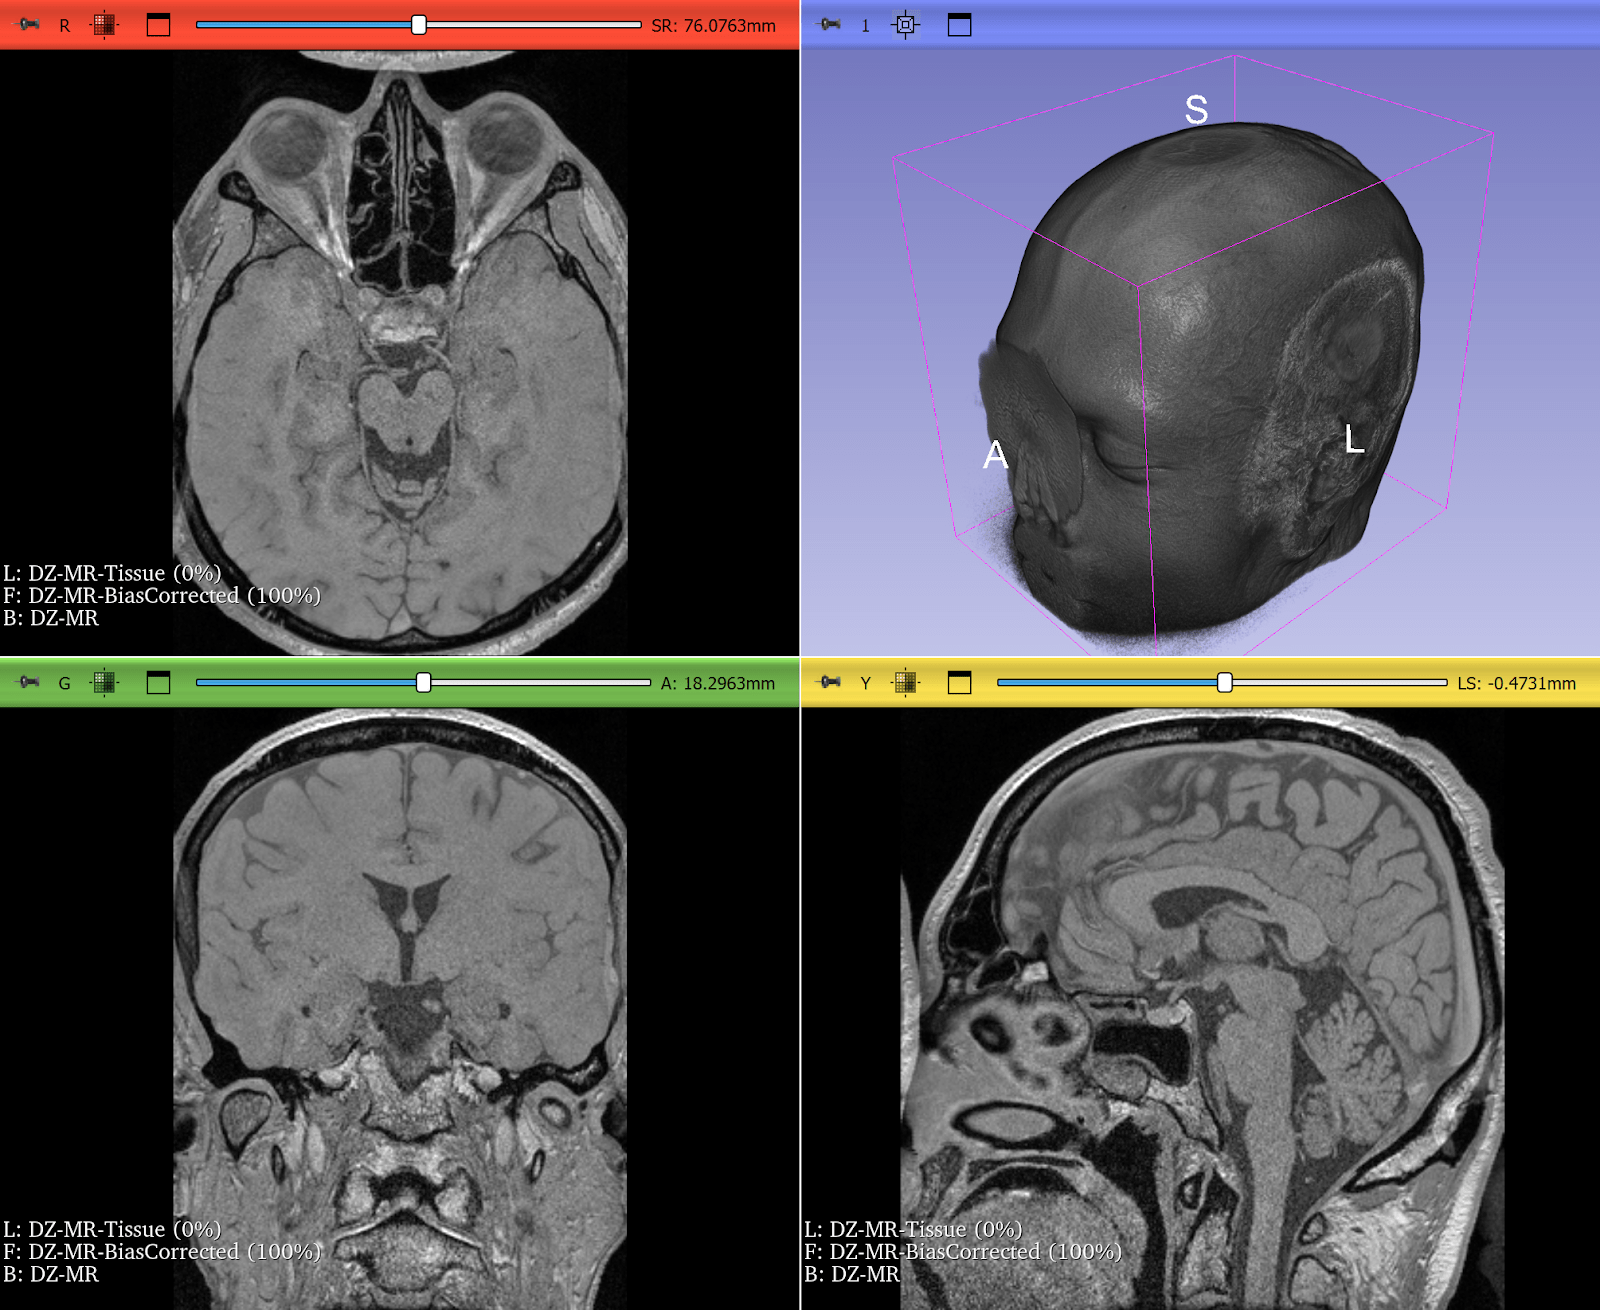

Bias Field Correction in Brain MRI

Magnetic resonance imaging (MRI) is prone to intensity inhomogeneities, also called bias fields. These low-frequency variations in intensity are not biological but caused by scanner physics. Deep learning models trained on uncorrected data risk learning scanner artifacts instead of tissue features.

ITK’s N4BiasFieldCorrectionImageFilter has become the gold standard for correcting this problem. With just a few lines of code, researchers can normalize the intensity profile of brain MRIs, making data consistent across scanners and institutions.

This correction is now a standard preprocessing step in brain tumor segmentation challenges and pipelines, ensuring that CNNs see consistent, biologically meaningful data. If a neural network is expected to encounter MRIs with intensity inhomogeneities, they can be intentionally introduced during training by using appropriate augmentation. Examples include RandBiasFieldd from MONAI and RandomBiasField from TorchIO. It can be even accomplished just by doing BiasFieldCorrection in reverse, starting from a corrected image and applying a randomly-generated bias field.

Figure 2: T2* Weighted MRI of the brain, before and after correction of intensity inhomogeneity. Bias field correction was done using 3D Slicer, another application prominently using ITK. Use left-right slider to compare before vs. after.